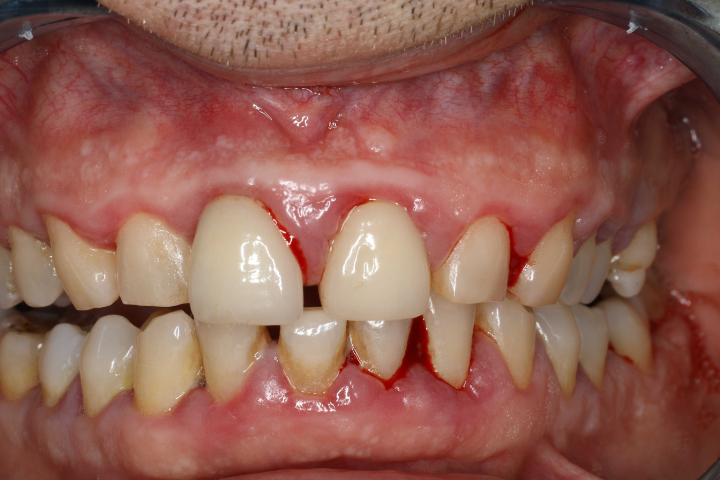

歯周病とは、歯と歯ぐきの境目にある歯周ポケットに細菌が繁殖し、歯ぐきや歯を支える骨に炎症を引き起こす病気です。初期段階では歯ぐきの腫れや出血といった症状が見られますが、進行すると歯を支える骨が溶け、最終的には歯が抜けてしまうこともあります。

歯周病は沈黙の病気とも呼ばれ、自覚症状が少ないまま進行するため、気づいたときには重度の状態にまで進行していることも少なくありません。

また、喫煙者の口腔内は乾燥しやすく、唾液の分泌量も減少するため、歯周病菌が繁殖しやすい環境が整ってしまいます。さらに、喫煙により炎症反応が鈍くなるため、出血などの自覚症状が現れにくく、歯周病が気づかないうちに進行するリスクが高くなります。

喫煙者は、非喫煙者に比べて歯周病にかかるリスクが2〜6倍に高まるという報告もあり、喫煙の影響は決して軽視できないことがわかります。